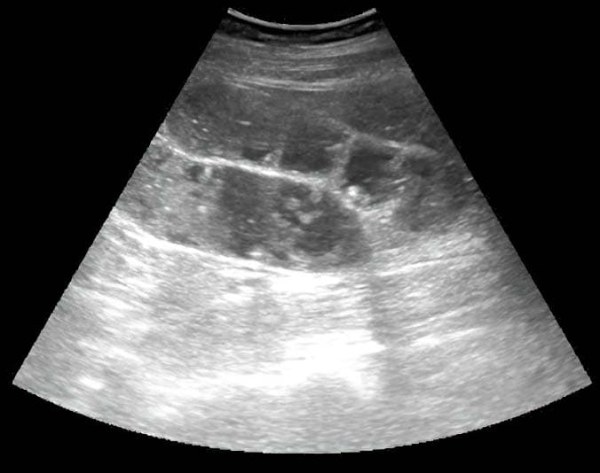

Аппендикулярный инфильтрат — это конгломерат спаянных между собой органов, располагающихся вокруг воспаленного червеобразного отростка, отграничивающих его от свободной брюшной полости (см. рис. 16). Аппендикулярный инфильтрат возникает у 3–5 % больных, как правило, спустя 4–5 суток от начала острого аппендицита. Аппендикулярный абсцесс возникает вследствие нагноения инфильтрата, перфорации аппендикса.

Из протокола УЗИ: «В правой подвздошной области визуализируется инфильтрат, определяется свободная жидкость межпетельно» (см. рис. 17).

Рисунок 17. УЗ-визуализация инфильтрата.

Из протокола операции: «Во всех отделах брюшной полости гной. Петли тонкой кишки раздуты, гиперемированы, отечны. В правой подвздошной ямке инфильтрат, состоящий из купола слепой кишки, червеобразного отростка, петли тонкой кишки, париетальной брюшины» (см. рис. 18).

Рисунок 18. Вскрытие абсцесса при разъединении инфильтрата в правой подвздошной области.